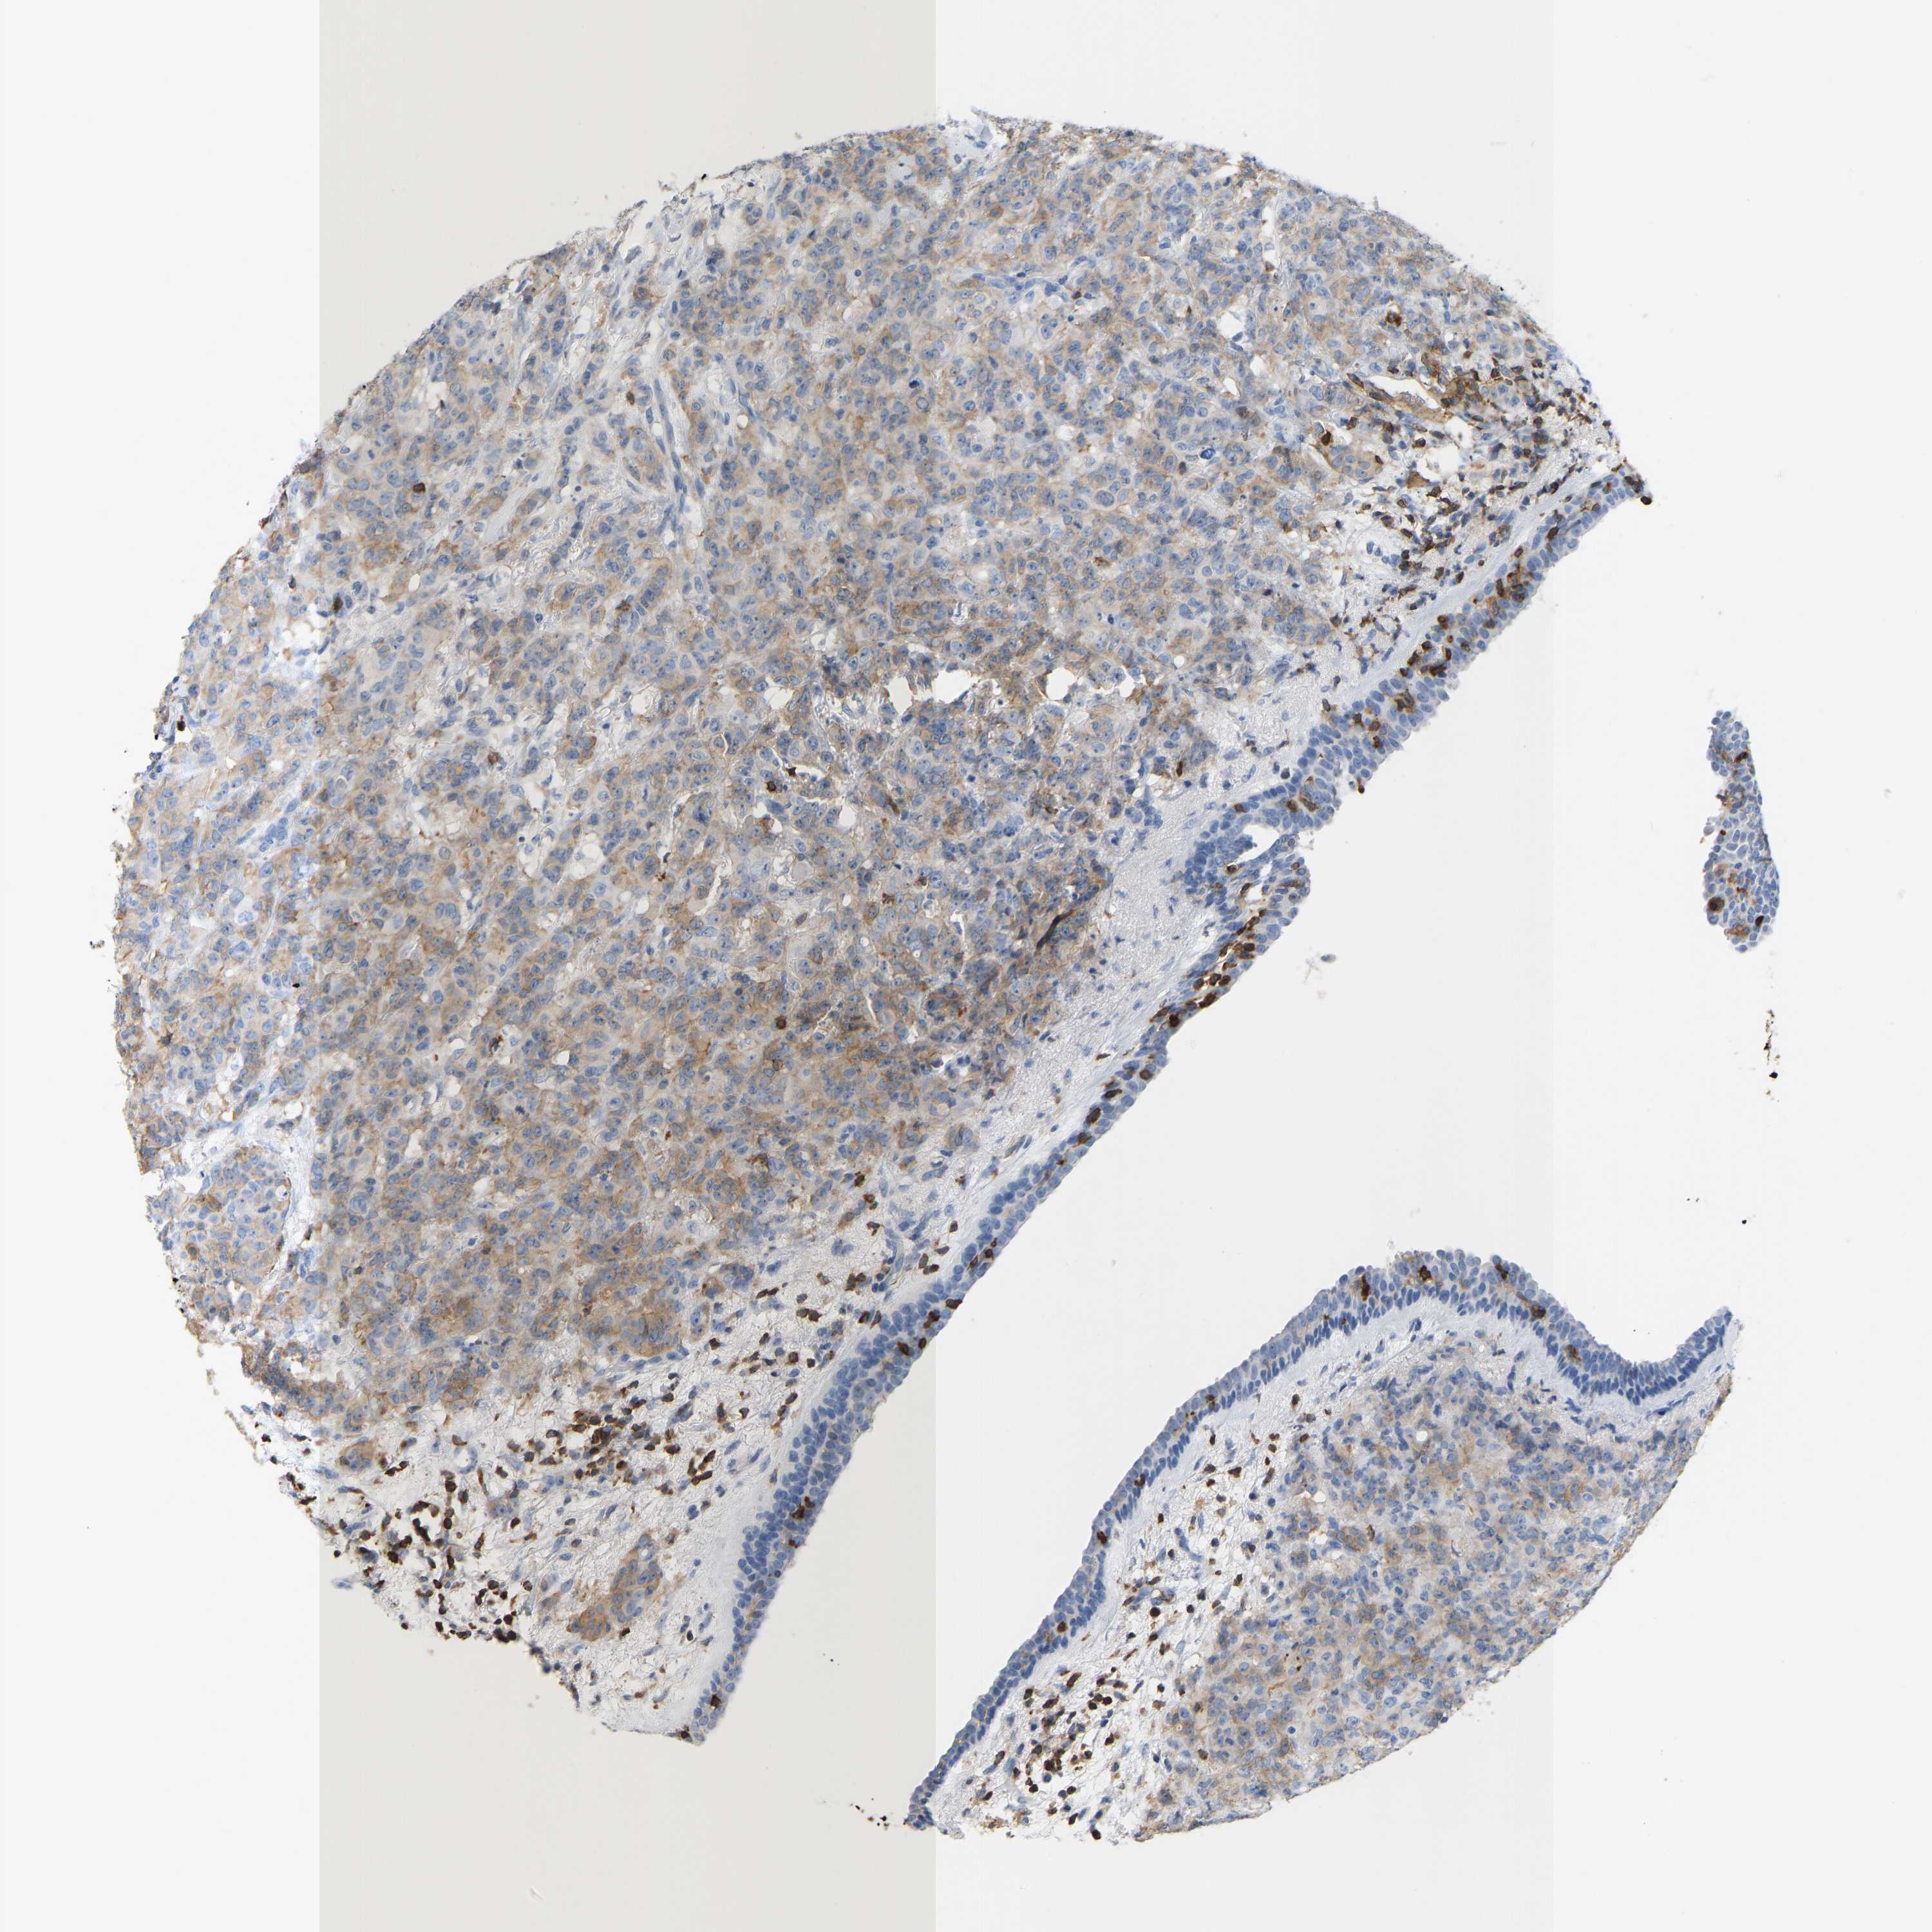

CANCER BREAST CANCER Show tissue menu

BRCA TCGA BRCA VALIDATION PROTEIN EXPRESSION

ANTIBODIES

AND

VALIDATION